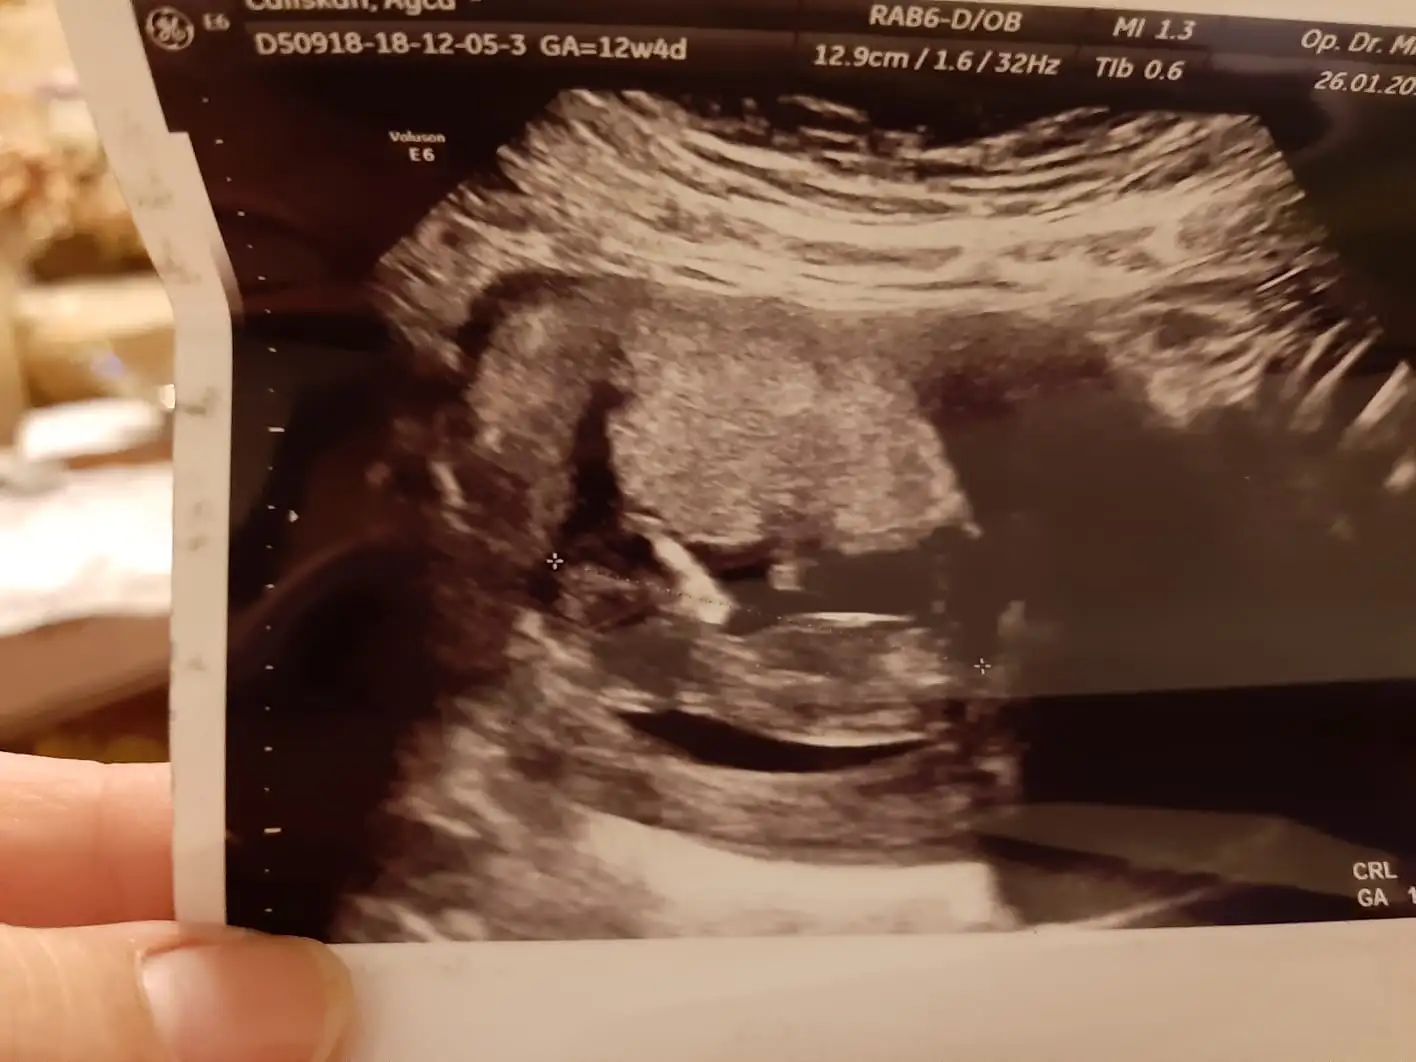

Kıza benziyor canm :)Arkadaşlar merhaba 11+5 günlüğüz cinsiyet tahmini yapabilir misiniz acaba nub teorisinden anlayan arkadaşlar yardımcı olabilirmi

erkeğe benziyor canım kıza göre biraz daha dikbanada tahminde bulunabilirmiisniz arkadaşlar Eki Görüntüle 2229364 rica etsem

ERKEK CANIMArkadaşlar merhaba 11+5 günlüğüz cinsiyet tahmini yapabilir misiniz acaba nub teorisinden anlayan arkadaşlar yardımcı olabilirmi